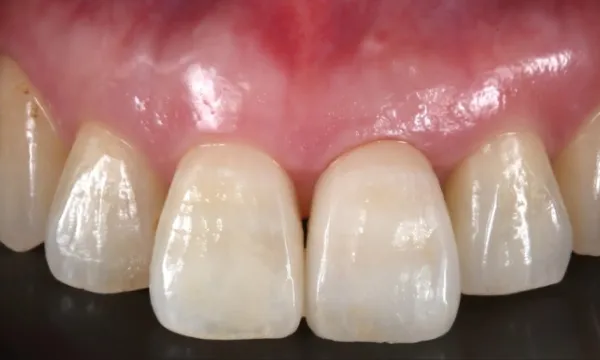

歯の欠損や見た目の不安は、笑顔や会話に大きな影響を与えます。「口を開けるのが恥ずかしい」「話すときに手で口元を隠してしまう」といったお悩みも少なくありません。全顎インプラント治療では、天然歯に近い色合いや形態の人工歯を用いることで、自然な口元を再現できます。見た目の改善はもちろん、食事の楽しさや会話のしやすさを取り戻すことにもつながります。

また、医療法人大杉歯科医院では治療前にCTや口腔内検査を用いた精密な診断を行い、骨や歯ぐきの状態を確認したうえで一人ひとりに合わせた治療計画を立てています。治療後も定期的なメンテナンスにより長期安定を目指し、安心して過ごしていただける体制を整えています。